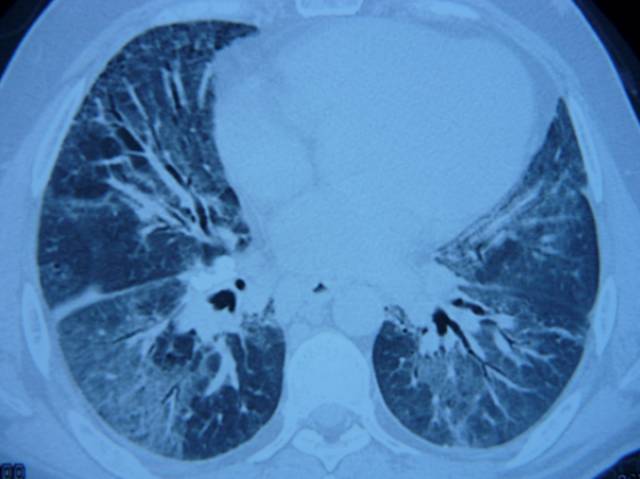

Es necesaria la valoración morfológica del pulmón mediante una Tomografía Computarizada (TC) de tórax para identificar signos sugestivos de la enfermedad. El diagnóstico definitivo se realiza mediante la observación de un pigmento característico en una biopsia del pulmón, o en algunos casos en el análisis del lavado bronquial; ambas técnicas realizadas mediante fibrobroncoscopia. El equipo médico es el encargado de valorar cuál es la metodología más idónea para cada paciente.